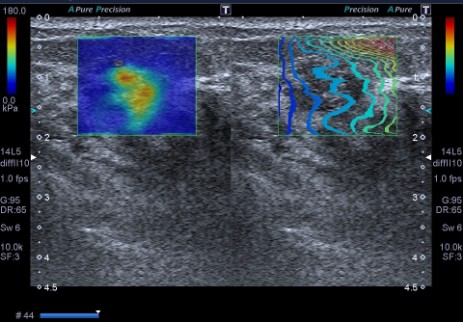

• Zasada działania: W przeciwieństwie do tradycyjnej elastografii (SE), SWE nie wymaga uciskania tkanki głowicą. Wykorzystuje ona impuls akustyczny do generowania fali poprzecznej, co zapewnia pełną obiektywizację i pomiary ilościowe w kPa lub m/s.

• Interpretacja: Twardsze tkanki (nowotwory) są wyświetlane na mapie kolorów inaczej niż tkanki miękkie (zmiany łagodne, torbiele).

Poniżej /fot. z badań własnych/ rak sutka w elastografii SWE